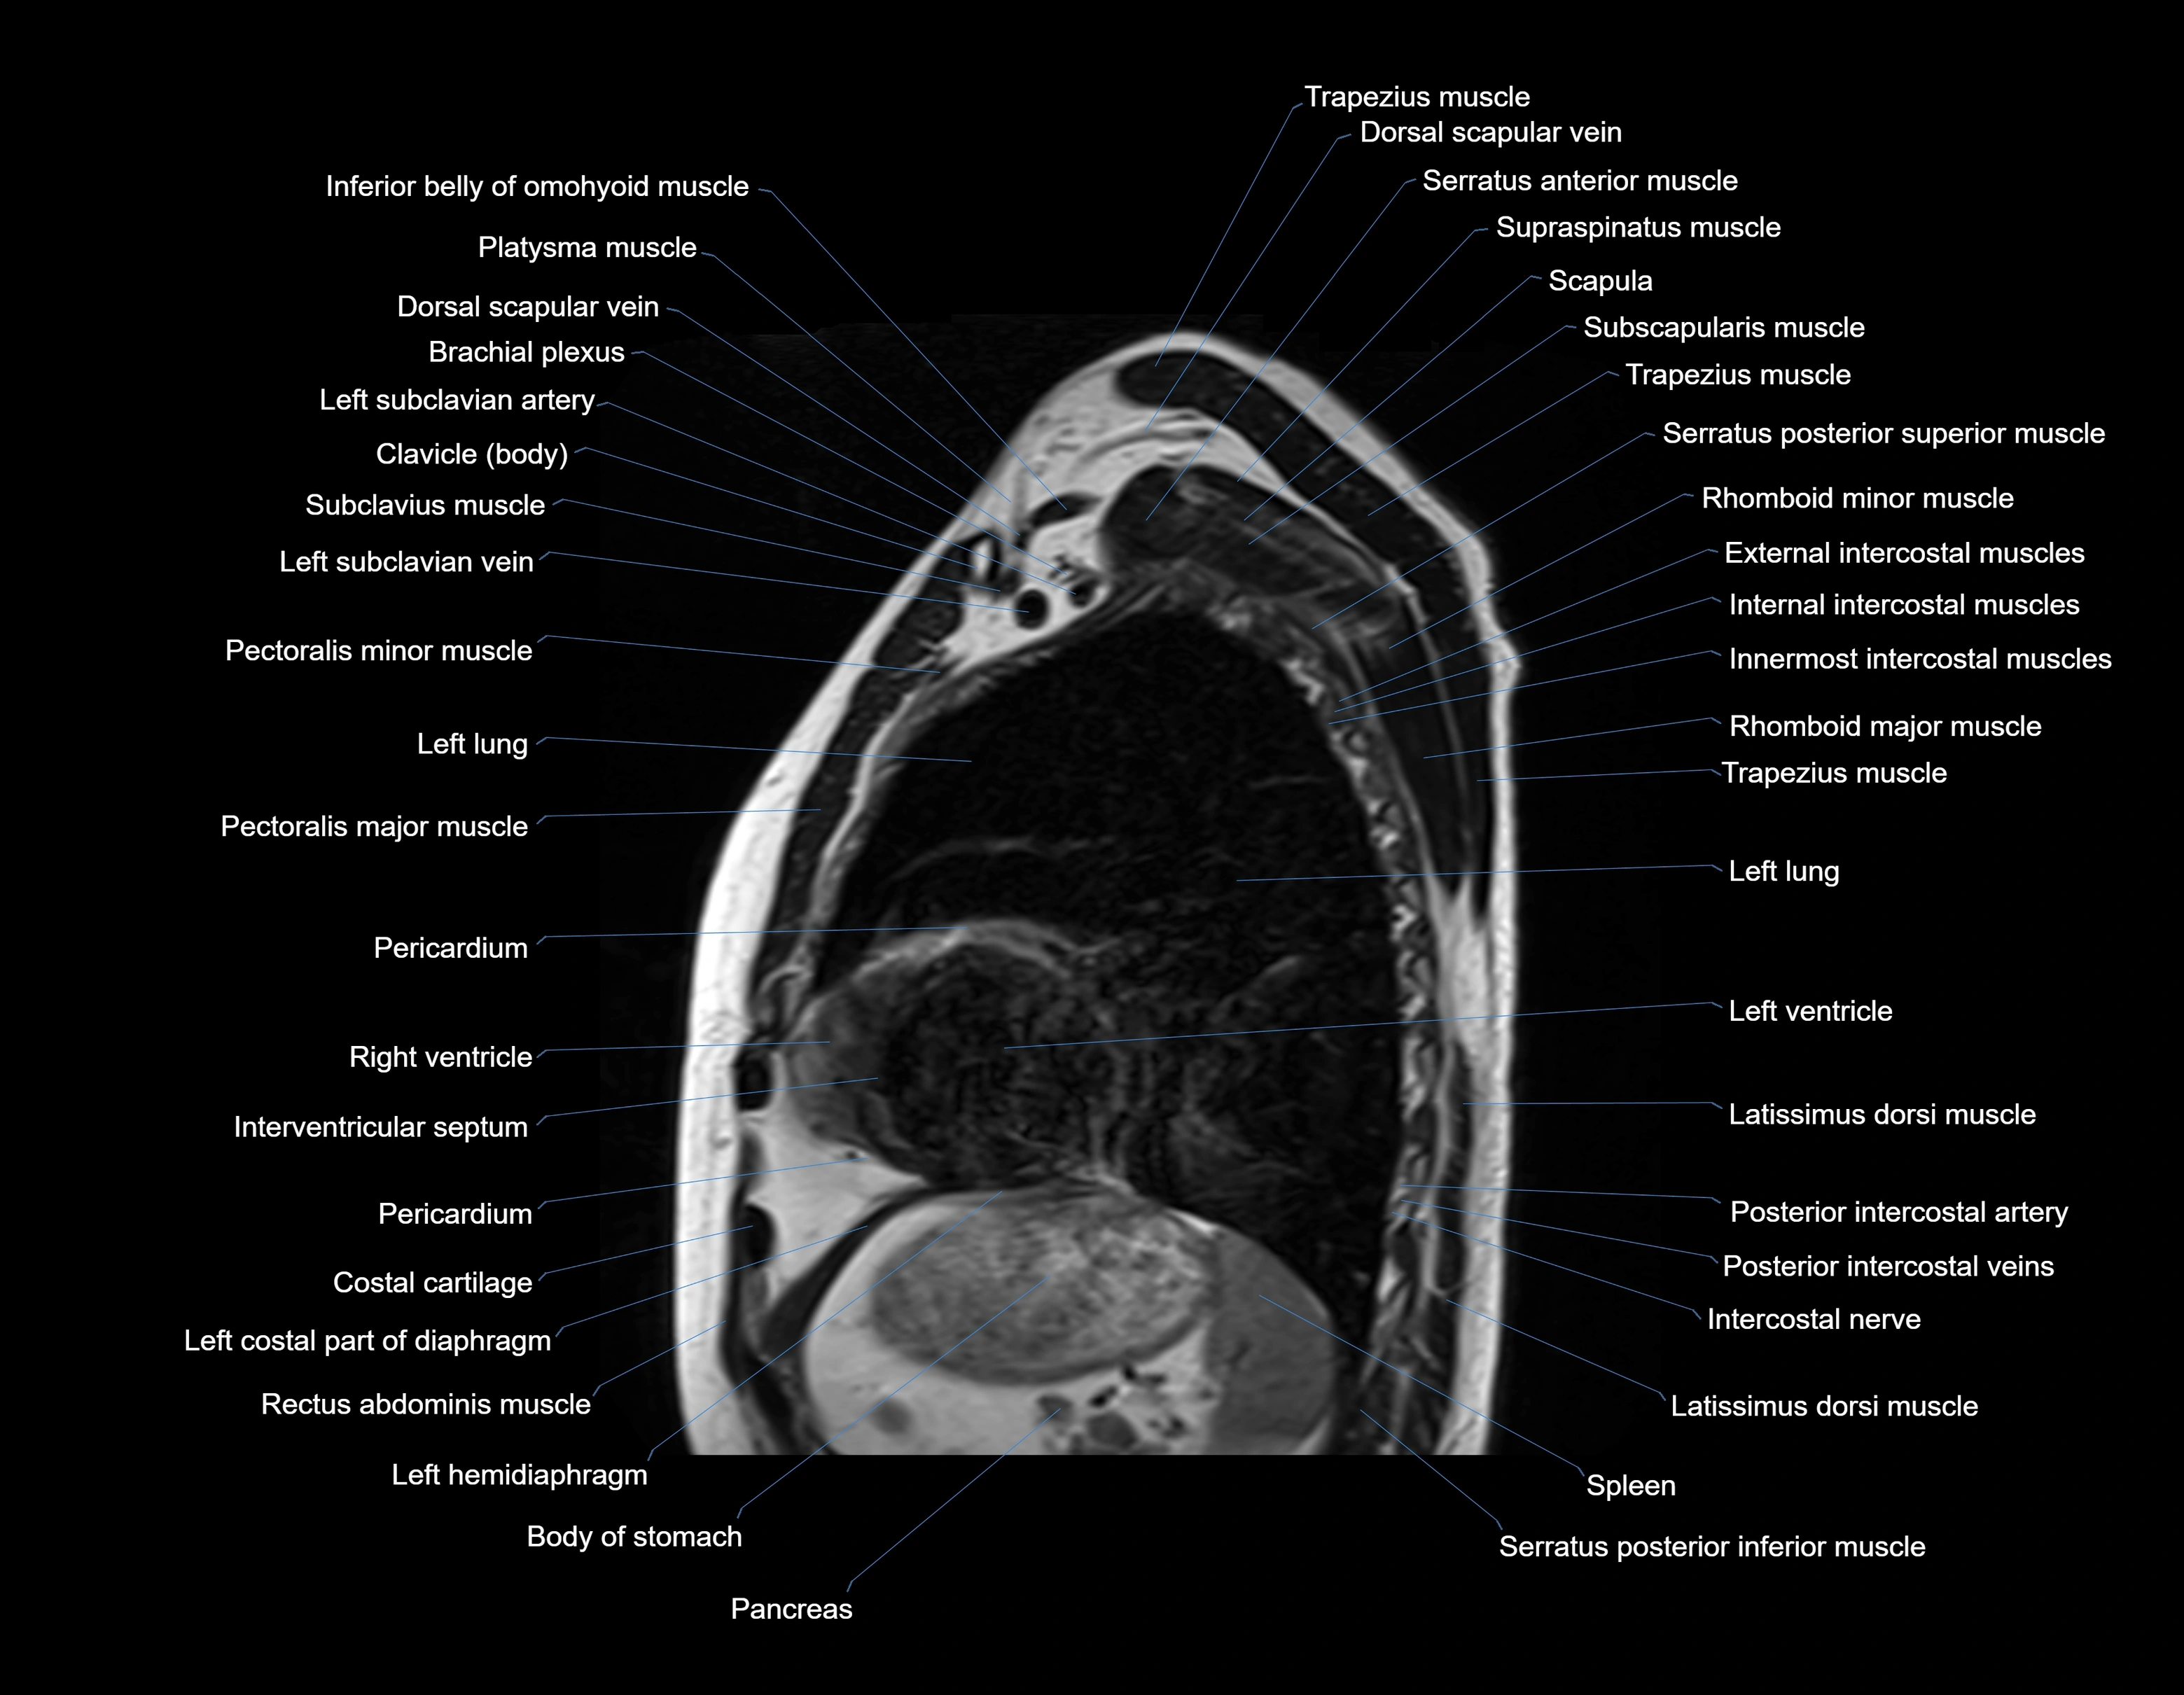

MRI images